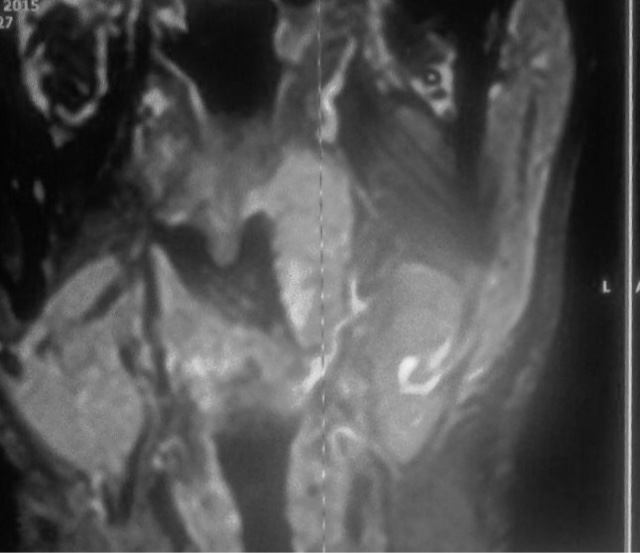

Tonsillar Mass-MRI

40 yr old male smoker with hx of right tonsillectomy 10 months for a tonsilar mass(HPE non- neoplastic), has recurrence in left tonsilar region wtih mixed signals and mass effect suggesting possible inflammatory pseudo tumour, with differential of lymphoproliferative aetiologies .

5. Cross sectional imaging may show tonsilar enlargement or grossly nodular thickening of nasopahrynx/ supra glottis with cervical lymphadenopathy. Radiology has no definite characteristics to exclude other aetiologies , though presence of necrosis/ tissues oedema/ enhancement on contrast may help.